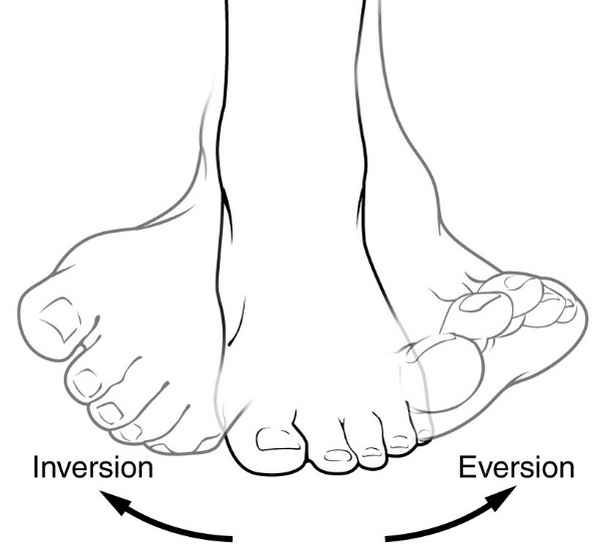

what are the motions of the subtalar joint?

inversion

eversion

rotation

in what plane does inversion and eversion of the foot occur?

frontal plane